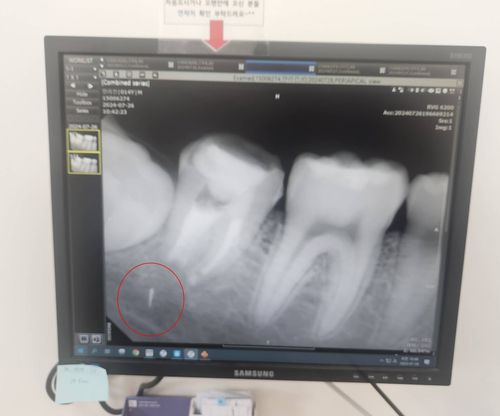

치과의원에서 신경치료를 받다가 파절된 의료기기 조각이 턱부위에 머무르고 있는 모습 [독자 제공. 재판매 및 DB 금지] |

그러나 치료 후에도 통증과 염증이 계속됐고, 한 달여 후 엑스레이 촬영을 통해 충격적인 사실을 확인했다. 치료 과정에서 부러진 의료기기 조각이 치아 뿌리에 남아 있었던 것이다. 안군의 성장에 따라 조각은 치아 뿌리에서 턱으로 서서히 이동하기까지 했다.

상급병원으로 옮긴 안군은 그해 가을 치아를 뽑고 턱뼈를 갈아내 조각을 제거한 뒤 다시 치아를 심는 수술대에 올랐다. 하지만 의료진은 수술 중 조각이 턱 신경과 너무 가까이 있어 무리하게 제거할 경우 신경 손상 위험이 크다고 판단했다. 결국 조각은 제거되지 못한 채 지금도 안군의 턱뼈 안에 박혀 있다.